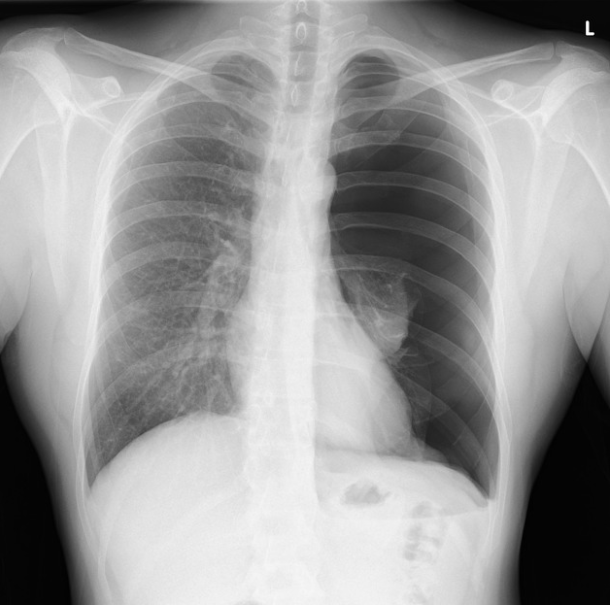

Pneumothorax

This x-ray shows a pneumothorax - which is air in the chest. See how the left lung (right on the image) is dark? It’s because the lung has collapsed.

The diagnosis given on radiopaedia.org is “Large left sided pneumothorax with total collapse of the left lung. Minor mediastinal shift. Heart size normal. Right lung clear.”

Grok recognized the left lung field was darker but missed the mark on its diagnosis.

ChatGPT does an excellent job.

Gemini did not do well at all.